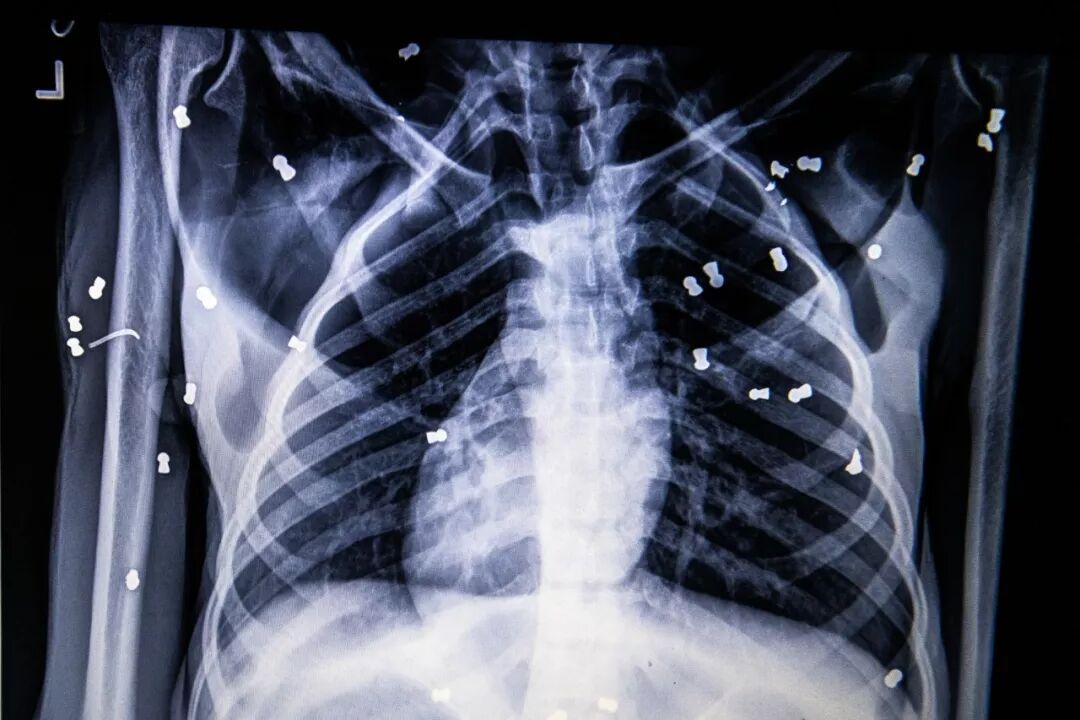

这是一位母亲的x光片,那些白点是她身体里的气步枪弹丸,右眼两颗,左眼四颗,此外还有多处骨折,被刀具刺伤。

仅仅因为吃了几个果子,她就被恶意驱赶,在被气步枪射中74次后,她终于被救了。

当他们发现猩猩妈妈时,倒在草丛里的她伤痕累累,直到送到医院才发现,她的身体里,遍布着74颗子弹,手和腿都严重骨折。

经过几次手术,猩猩妈妈终于活下来了,他们为她取名叫Hope。